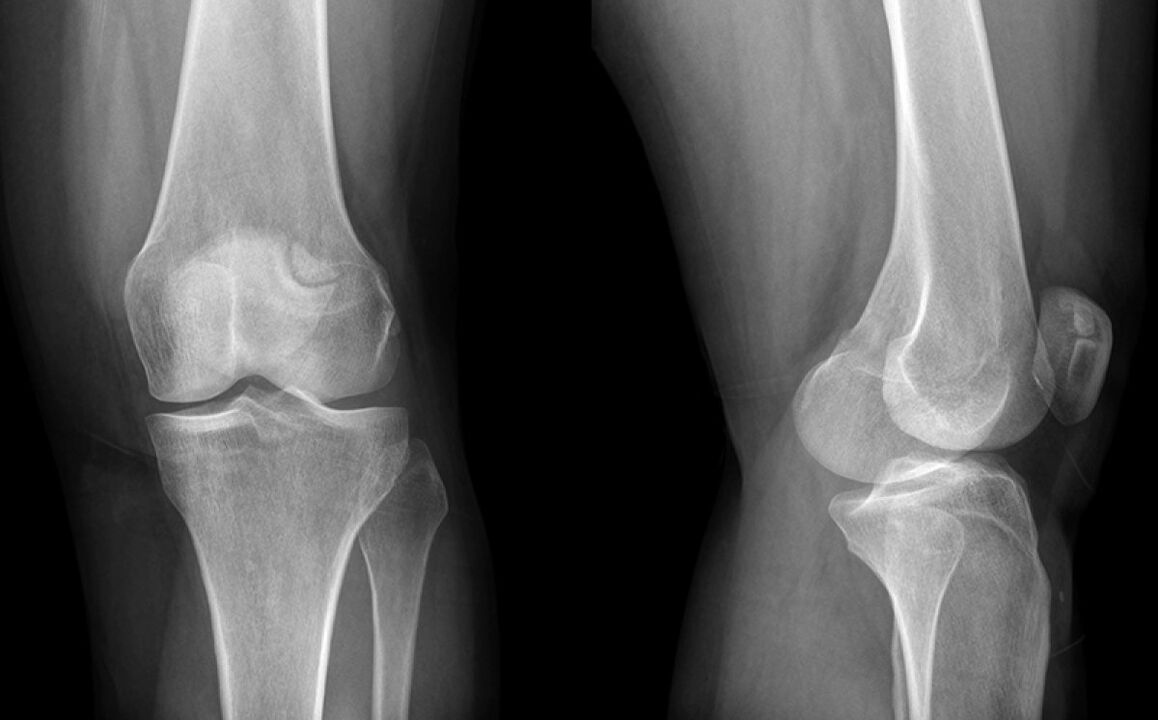

Kelias skaudėjo tris savaites. Galų gale nuvykau pas gydytoją, kuris įtarė menisko žalą ir išsiuntė į X -LAY. Diagnozė yra pradinė kelio sąnario artrozės stadija.